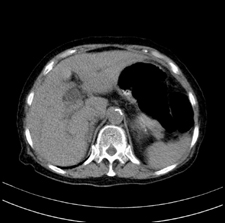

患者,女,75岁。腹痛,体黄5日,膝胸位时腹痛缓解。肝功能明日出来。彩超提示胆总管占位,未见血流信号。心电图提示s-t段改变。患者体质较弱,未能增强。

肝囊右.肾上腺囊肿

支持 胆总管结石,左侧胸膜增厚,心包膜增厚。